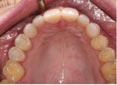

1. What injury can be diagnosed from the teledentistry photo (below), and what is the importance of timely surgery attendance for this type of injury?